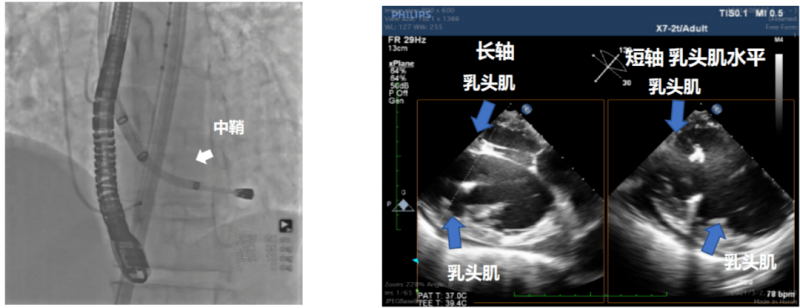

行业中,经导管心内微创手术一般通过穿刺股动脉建立器械通路,在X线透视引导下将注射系统送入左心室。而德柯医疗独特设计的心内膜注射系统,可以在经食道超声(TEE)引导下,头端抵近预先设定的左心室游离壁靶区域,并完成水凝胶的安全植入。

1)通过TEE引导,调整鞘内位置

2)明确注射系统与心室壁形成良好稳定的接触

3)通过造影剂和超声双重确认注射针安全刺入心室壁心肌

4 )TEE验证水凝胶成功保留于左心室壁